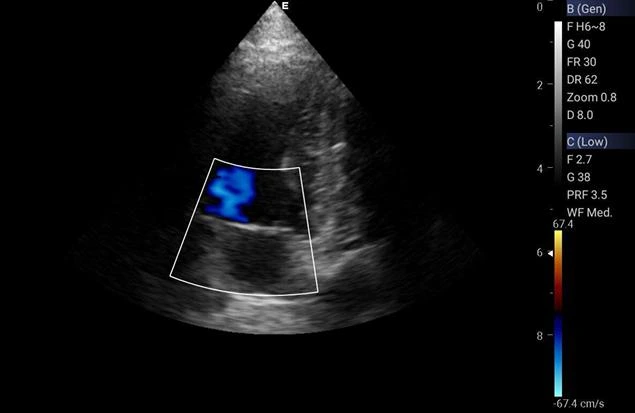

A ecocardiografia veterinária é um exame completo e não invasivo que utiliza ultrassom para avaliar o coração e as estruturas circundantes dos animais.

O Biota Centro de Diagnóstico Veterinário oferece esse serviço especializado para garantir o diagnóstico preciso de possíveis doenças cardíacas em pets.

Com equipamentos adequados e uma equipe altamente qualificada, O Biota Centro de Diagnóstico Veterinário se destaca por proporcionar um atendimento de excelência e cuidados específicos para cada paciente.

A ecocardiografia é essencial para detectar precocemente problemas cardíacos nos animais, permitindo um tratamento adequado e aumentando a qualidade de vida do pet.